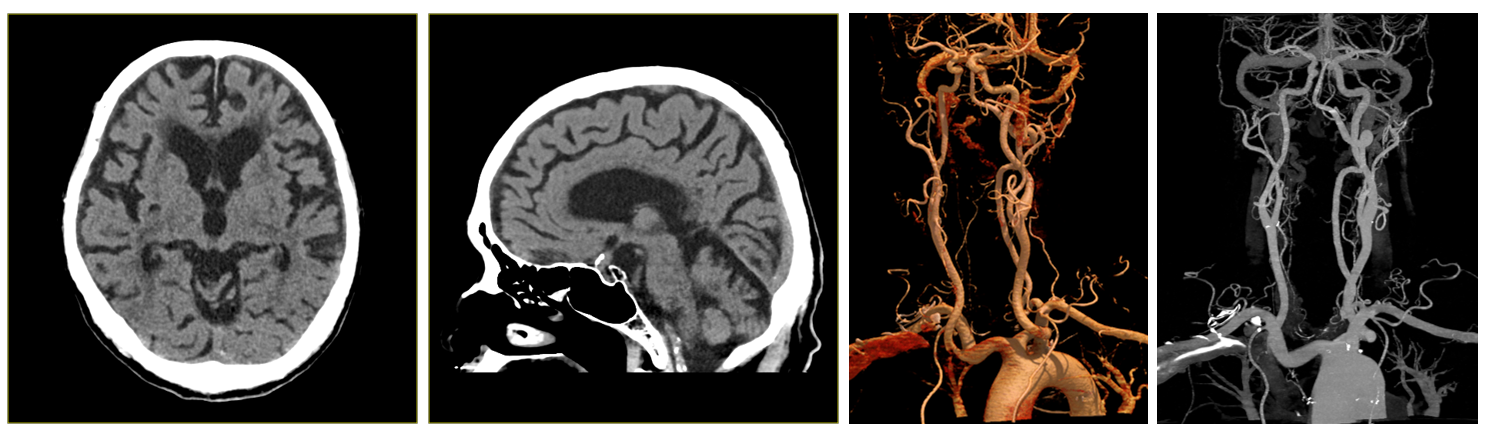

뇌혈관 검사 특화 기술 : 캐논만의 독자적인 기술인 SURE Subtraction Brain으로 뇌혈관부터 경동맥까지 선명히 구현 가능